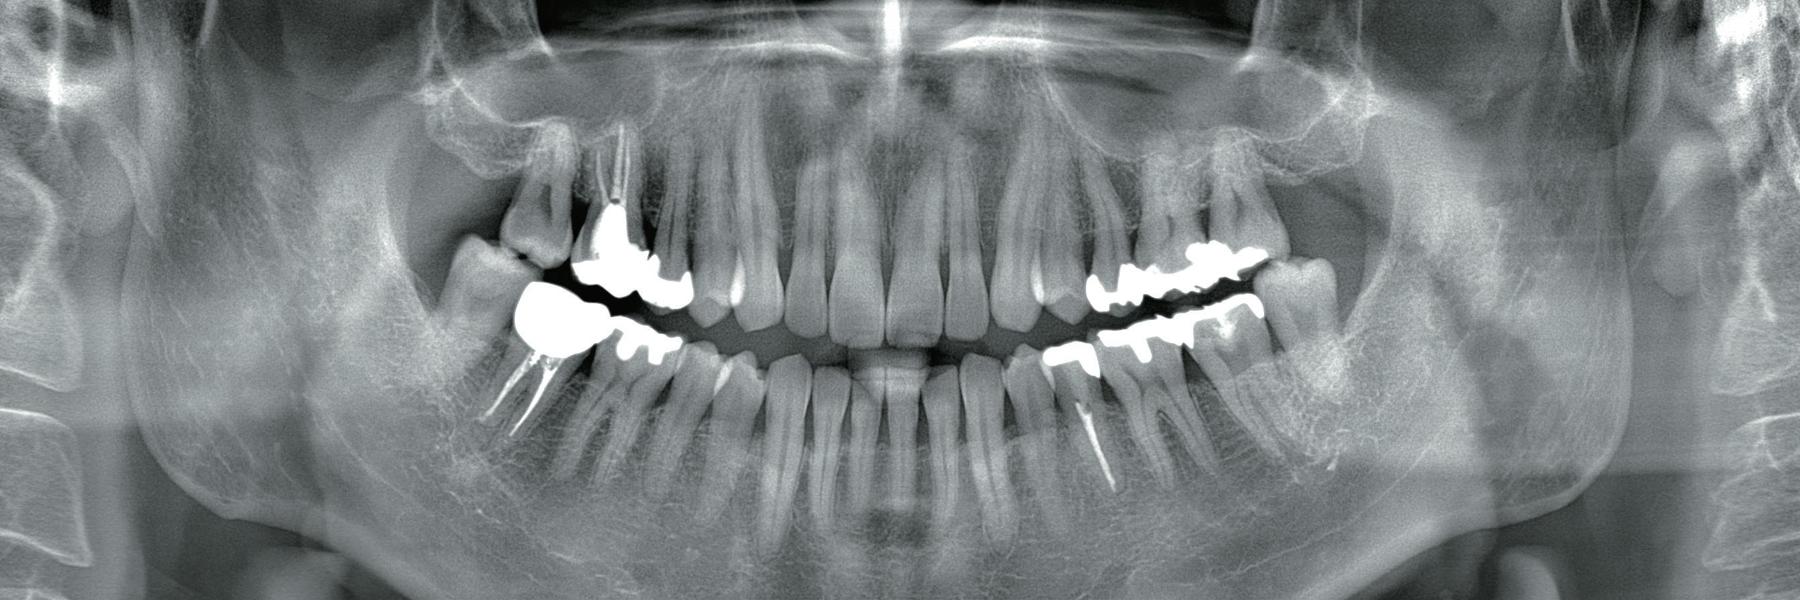

- X-rays